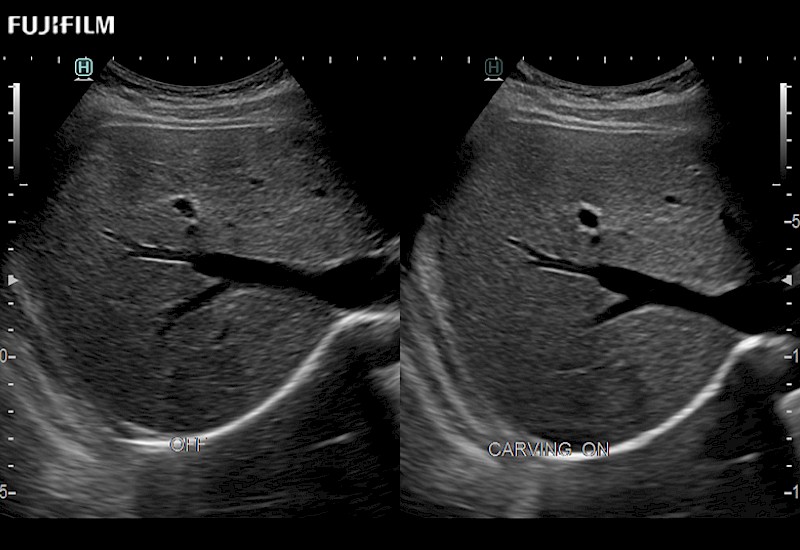

The ARIETTA 750 incorporates all of the proven technologies and functions that medical professionals have come to expect from Fujifilm Healthcare.

ARIETTA 750 is the definitive diagnostic ultrasound solution for any clinical setting - Private Office, Imaging Center, or Hospital. The ARIETTA platform provides the ultimate in clinical performance with its state-of-the-art features and large user-friendly display.

The ARIETTA 650 DI combines trusted Fujifilm Healthcare technologies and features tailored for surgical oncology.

Designed to meet the demands of surgeons, the ARIETTA 650 DI offers precise guidance. Its advanced capabilities and large, intuitive display offer accurate and efficient care in operating rooms and specialized surgical settings.